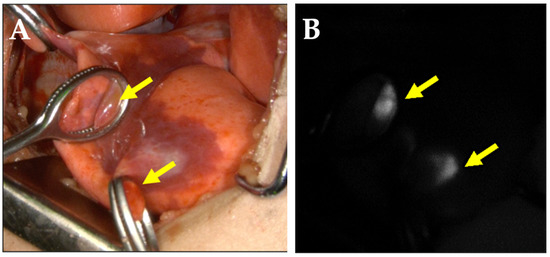

- Kitagawa, N.; Shinkai, M.; Mochizuki, K.; Usui, H.; Miyagi, H.; Nakamura, K.; Tanaka, M.; Tanaka, Y.; Kusano, M.; Ohtsubo, S. Navigation using indocyanine green fluorescence imaging for hepatoblastoma pulmonary metastases surgery. Pediatr. Surg. Int. 2015, 31, 407–411. [Google Scholar] [CrossRef]

- Yamamichi, T.; Oue, T.; Yonekura, T.; Owari, M.; Nakahata, K.; Umeda, S.; Nara, K.; Ueno, T.; Uehara, S.; Usui, N. Clinical application of indocyanine green (ICG) fluorescent imaging of hepatoblastoma. J. Pediatr. Surg. 2015, 50, 833–836. [Google Scholar] [CrossRef] [PubMed]

- Cho, Y.J.; Namgoong, J.M.; Kwon, H.H.; Kwon, Y.J.; Kim, D.Y.; Kim, S.C. The Advantages of Indocyanine Green Fluorescence Imaging in Detecting and Treating Pediatric Hepatoblastoma: A Preliminary Experience. Front. Pediatr. 2021, 9, 635394. [Google Scholar] [CrossRef] [PubMed]

- Yamada, Y.; Ohno, M.; Fujino, A.; Kanamori, Y.; Irie, R.; Yoshioka, T.; Miyazaki, O.; Uchida, H.; Fukuda, A.; Sakamoto, S.; et al. Fluorescence-Guided Surgery for Hepatoblastoma with Indocyanine Green. Cancers 2019, 11, 1215. [Google Scholar] [CrossRef] [Green Version]

- Souzaki, R.; Kawakubo, N.; Matsuura, T.; Yoshimaru, K.; Koga, Y.; Takemoto, J.; Shibui, Y.; Kohashi, K.; Hayashida, M.; Oda, Y.; et al. Navigation surgery using indocyanine green fluorescent imaging for hepatoblastoma patients. Pediatr. Surg. Int. 2019, 35, 551–557. [Google Scholar] [CrossRef]